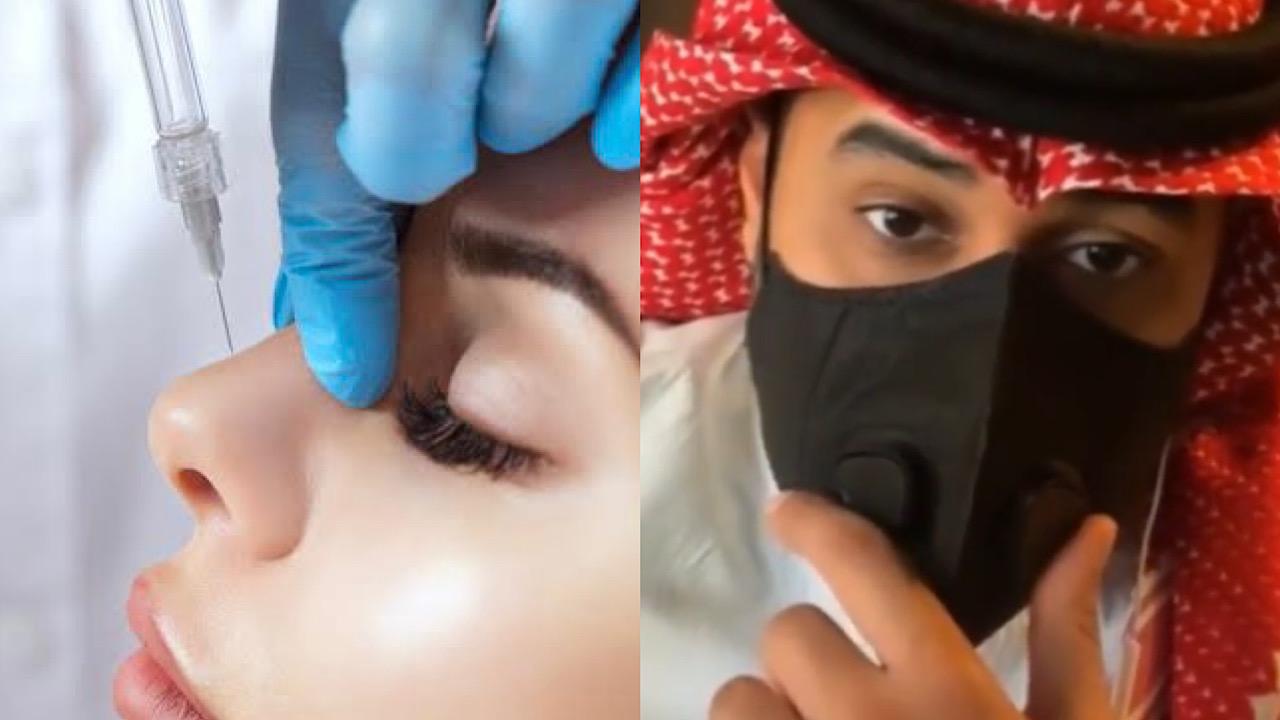

فتاة في حالة إنهيار : فقدت بصري بسبب إبرة فيلر أخذتها في أنفي ..فيديو